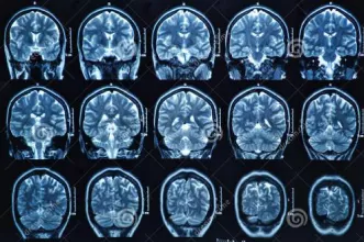

MRI也就是磁共振成像,屬于斷層成像的一種,它是利用磁共振現(xiàn)象從人體中獲得電磁信號(hào),并重建出人體信息。通過檢查可獲得橫斷面、矢狀面、冠狀面的影像,空間分辨率高,是神經(jīng)系統(tǒng)、脊柱脊椎部分檢測(cè)的第一選擇。

無論是DR還是CT,由于對(duì)部分軟組織的分辨率不足,所以軟組織疾病的排查便成了它們的短板,而磁共振的長(zhǎng)處恰恰就是清晰顯示軟組織疾病,對(duì)于膀胱、直腸、子宮及關(guān)節(jié)肌肉的檢查優(yōu)于CT。MRI適用于神經(jīng)系統(tǒng)病變、心血管系統(tǒng)、胸部病變、全身軟組織病變等。